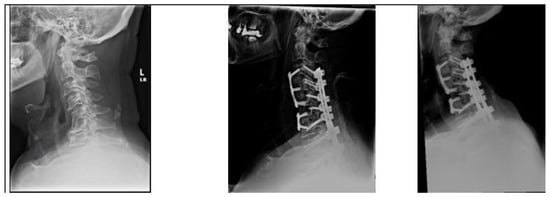

Figure 3.

A 70-year-old male from the non-DJK group. Images from left-to-right: preoperative, immediate postoperative, and 3-month postoperative X-rays. History of intractable neck pain with sensory and motor right upper limb deficits. Had also previously undergone L2-to-pelvis fusion for degenerative lumbar disc disease. Underwent C3–C5 and C6–C7 ACDF with C3-T2 posterior fusion. Symptoms showed improvement and radiographic alignment was maintained without evidence of DJK.